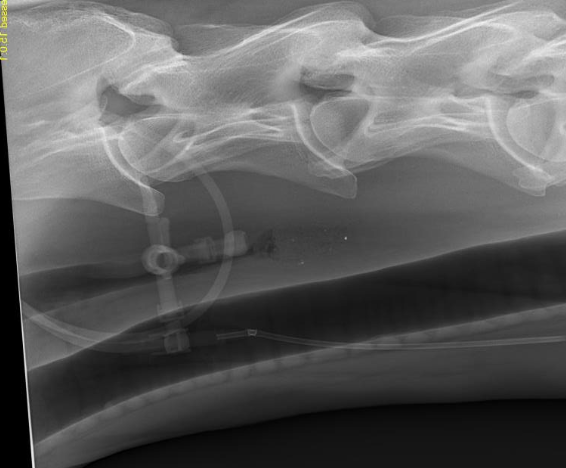

can help identify:

-location and length of obstruction

-evidence of esophageal rupture

-esophageal abnormalities (diverticulum, megaesophagus, stricture)

-assess lungs